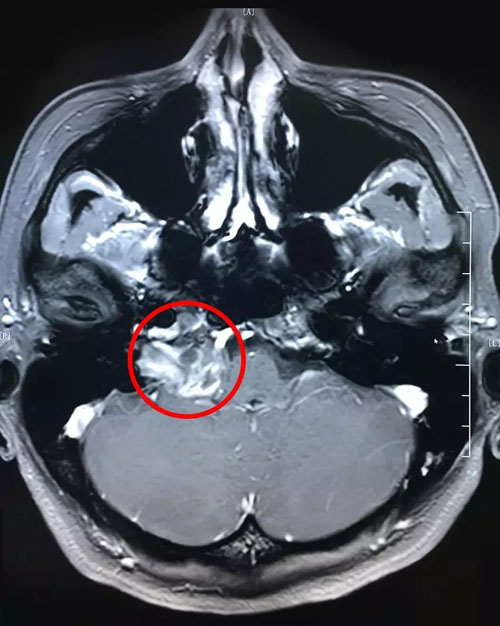

从最新的影像资料上来看,患者右侧桥小脑区占位、颈深部占位,神经鞘瘤的可能性很大。

患者术前影像:右侧桥小脑区占位,颈深部占位